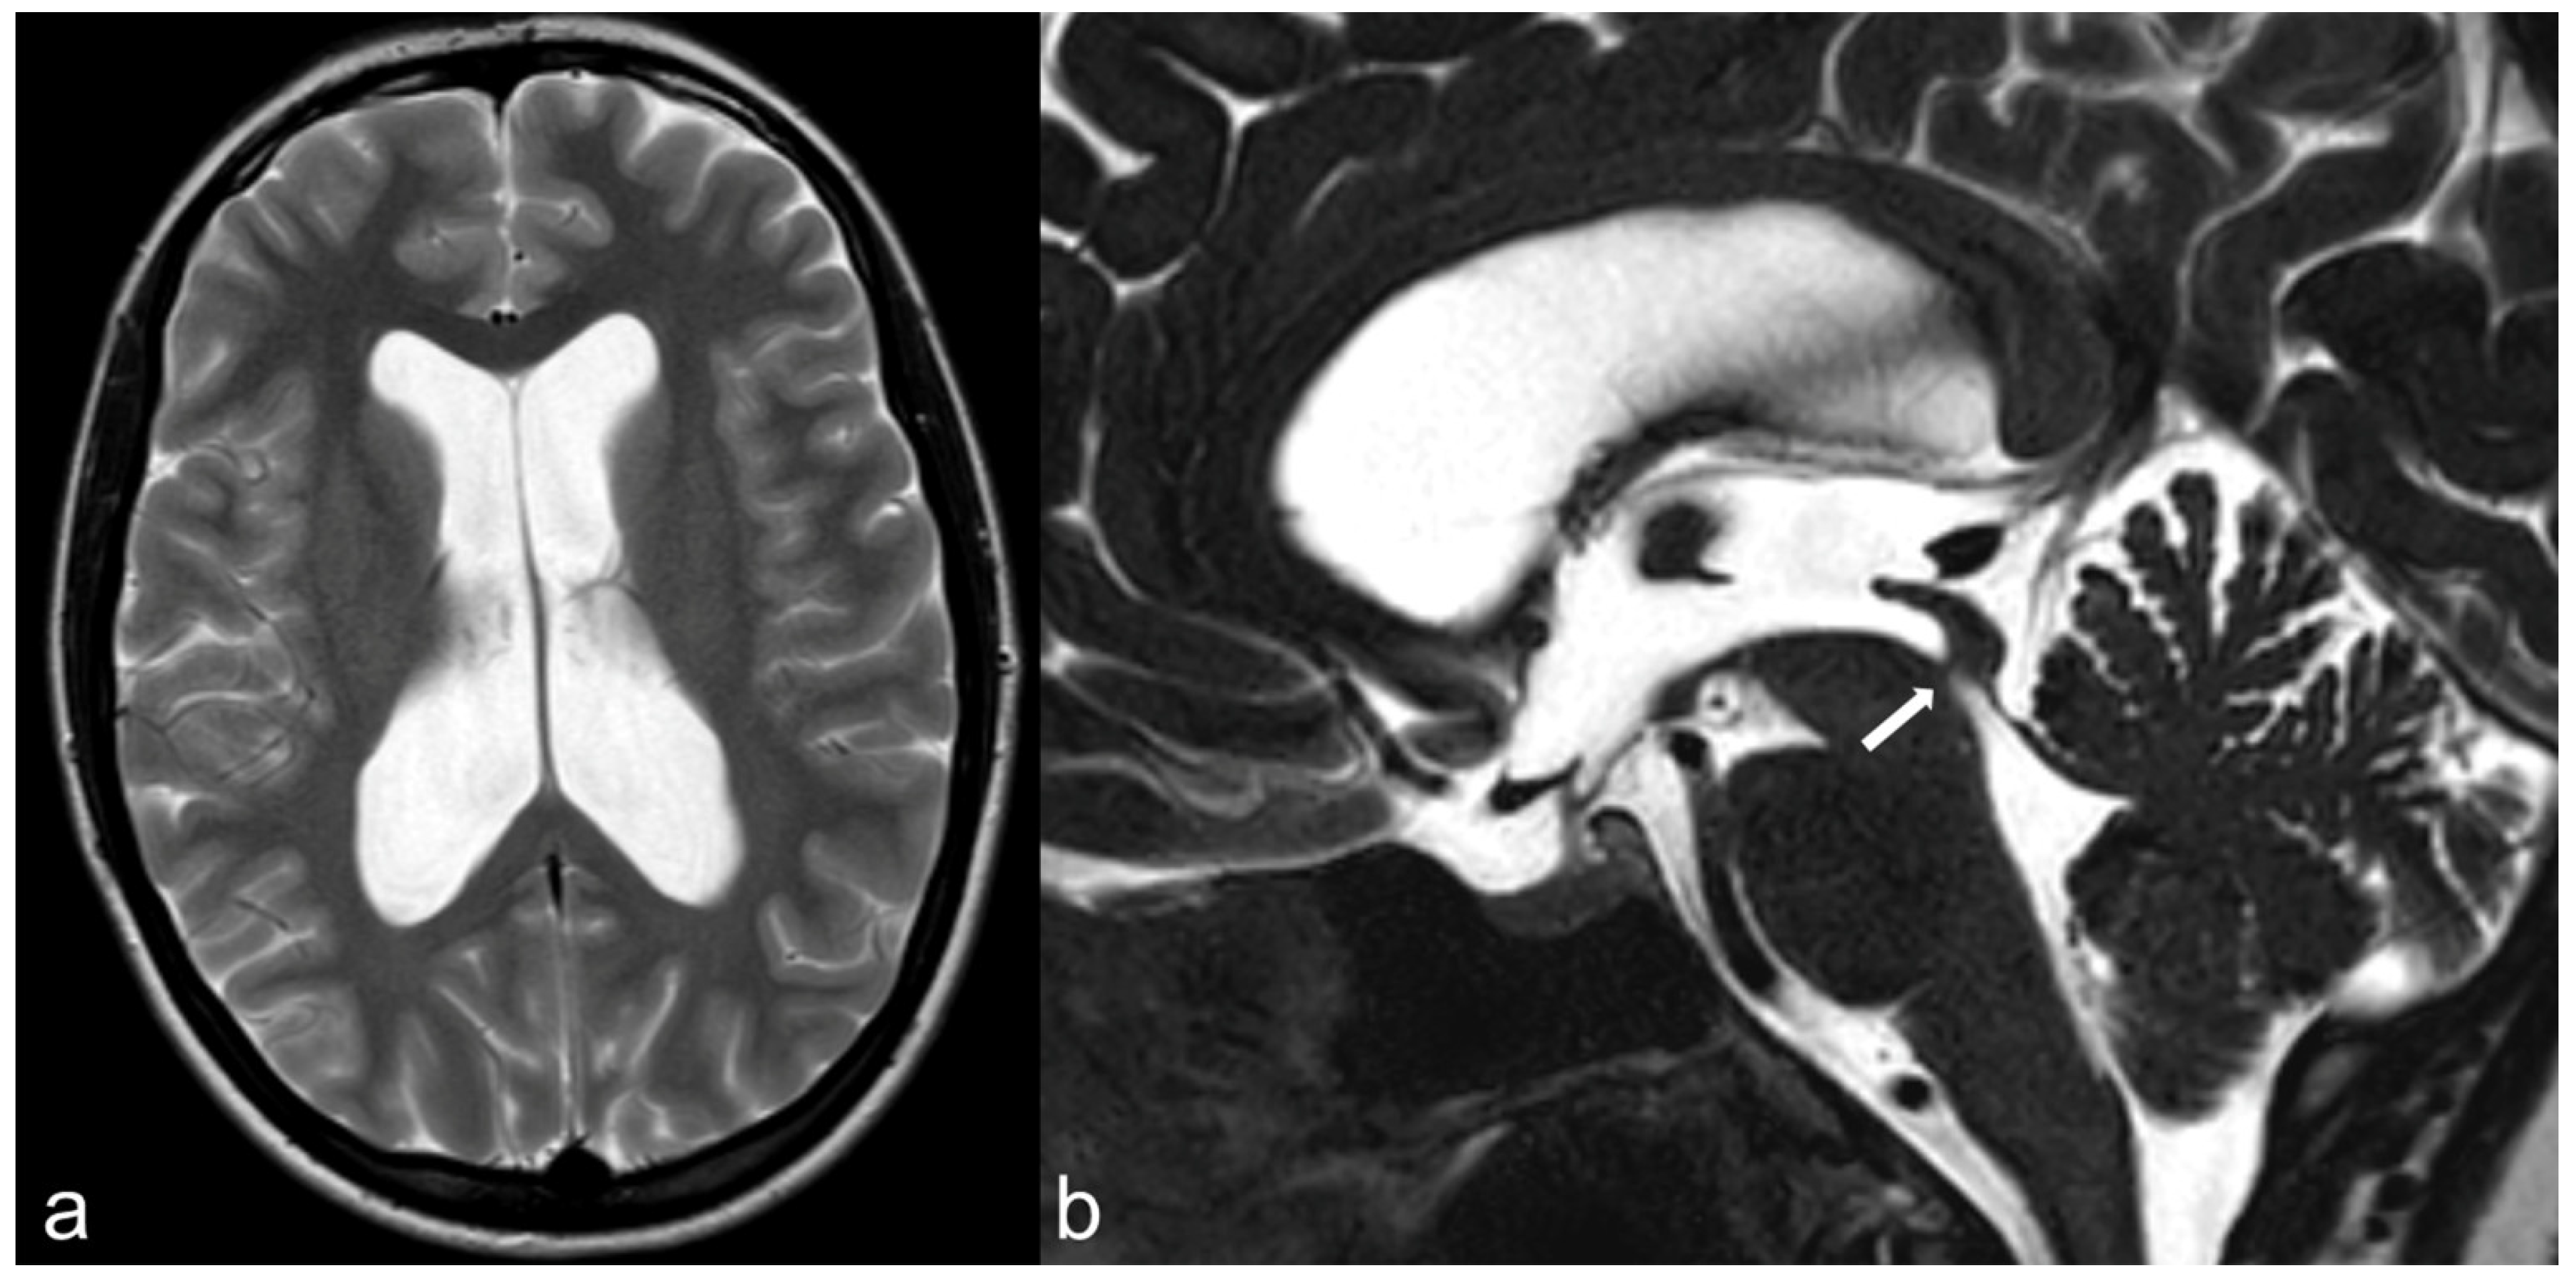

3.5. Hydrocephalus, Ventricular System and Subarachnoid Cisterns

- Da Costa Val Filho, J.A.; da Silva Gusmão, S.N.; Furtado, L.M.F.; de Macedo Machado Filho, G.; Maciel, F.L.A. The role of the Liliequist membrane in the third ventriculostomy. Neurosurg. Rev. 2021, 44, 3375–3385. [Google Scholar] [CrossRef] [PubMed]

- Fushimi, Y.; Miki, Y.; Ueba, T.; Kanagaki, M.; Takahashi, T.; Yamamoto, A.; Haque, T.L.; Konishi, J.; Takahashi, J.A.; Hashimoto, N.; et al. Liliequist membrane: Three-dimensional constructive interference in steady state MR imaging. Radiology 2003, 229, 360–365, discussion 365. [Google Scholar] [CrossRef] [PubMed]

- Dias, D.A.; Castro, F.L.; Yared, J.H.; Lucas Júnior, A.; Ferreira Filho, L.A.; Ferreira, N.F. Liliequist membrane: Radiological evaluation, clinical and therapeutic implications. Radiol. Bras. 2014, 47, 182–185. [Google Scholar] [CrossRef] [PubMed]

- Siow, T.Y.; Chuang, C.C.; Toh, C.H.; Castillo, M. Persisting Embryonal Infundibular Recess: Case Report and Imaging Findings. World Neurosurg. 2018, 117, 11–14. [Google Scholar] [CrossRef]